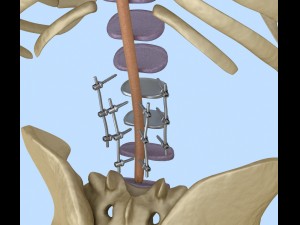

spinal fixation system - titanium bracket 3D 모델

spinal fixation system - titanium bracket. human spine, spinal cord, sacrum and fixation system medically accurate high quality 3d model.

hi-poly 3d model of human spine with internal structure.